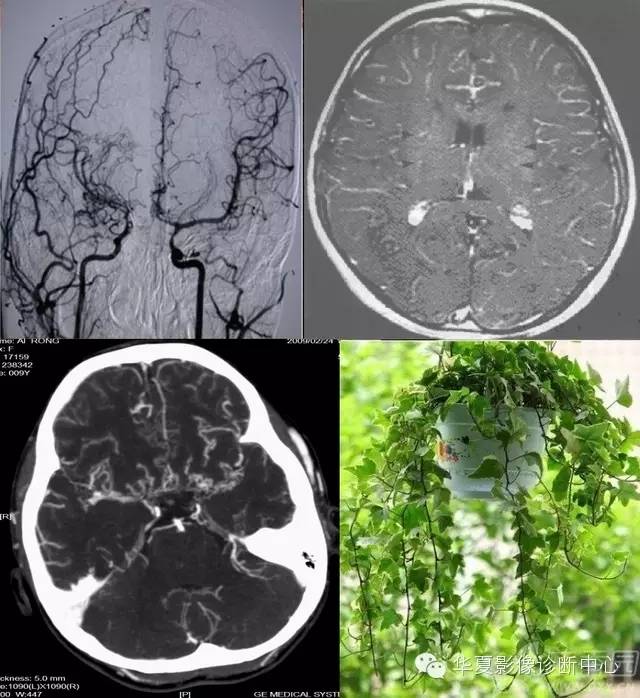

常春藤征

该征是指烟雾病患者MR检查增强扫描时图像上观察到沿柔脑膜分布的点状或线状强化信号影,因类似爬行在石头上的常春藤而命名。文献报道这种征象出现率约70%,并提出其对烟雾病的诊断具有特异性。其形成主要是双侧颈内动脉、大脑前、中动脉狭窄或闭塞后,颈外动脉及椎-基底动脉系统参与代偿性供血的侧支循环血管,包括大脑后动脉、脑膜中动脉、颞浅动脉、枕动脉,沿双侧大脑皮层柔脑膜分布。有研究报道FLAIR图像亦可观察到常春藤征,表现为柔脑膜弥漫性高信号改变。FLAIR序列是水信号为零时的反转脉冲序列,由于FLAIR能够有效地克服脑脊液在T2WI呈高信号所致的部分容积效应和伪影的影响,敏感地反映蛛网膜下腔轻微信号强度的改变,对蛛网膜下腔病变如蛛网膜下腔出血、脑膜炎和脑膜转移瘤等比常规T2WI敏感。在烟雾病患者FLAIR图像上的常春藤征的产生机制仍未完全清楚,目前存在几种不同的说法:

这种表现是由于颈内动脉及大脑中动脉狭窄、闭塞后,颈外动脉及椎-基底动脉系统参与代偿性供血,通过DSA检查可见扩张的颈外动脉系统及大脑后动脉参与形成的柔脑膜侧支血管网,颈内动脉狭窄或闭塞程度越严重,柔脑膜高信号的范围越广泛,其常春藤征表现越明显。常春藤征的轻重与病情进展情况有关。根据DSA表现,烟雾病的病程分为6个阶段: